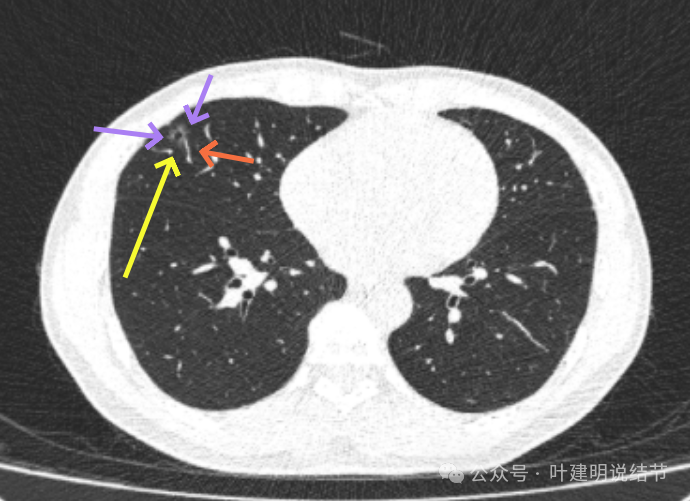

2022年11月时,病灶较前范围有所扩大,表面现分叶征,灶内有血管穿行,轮廓与边界清楚。